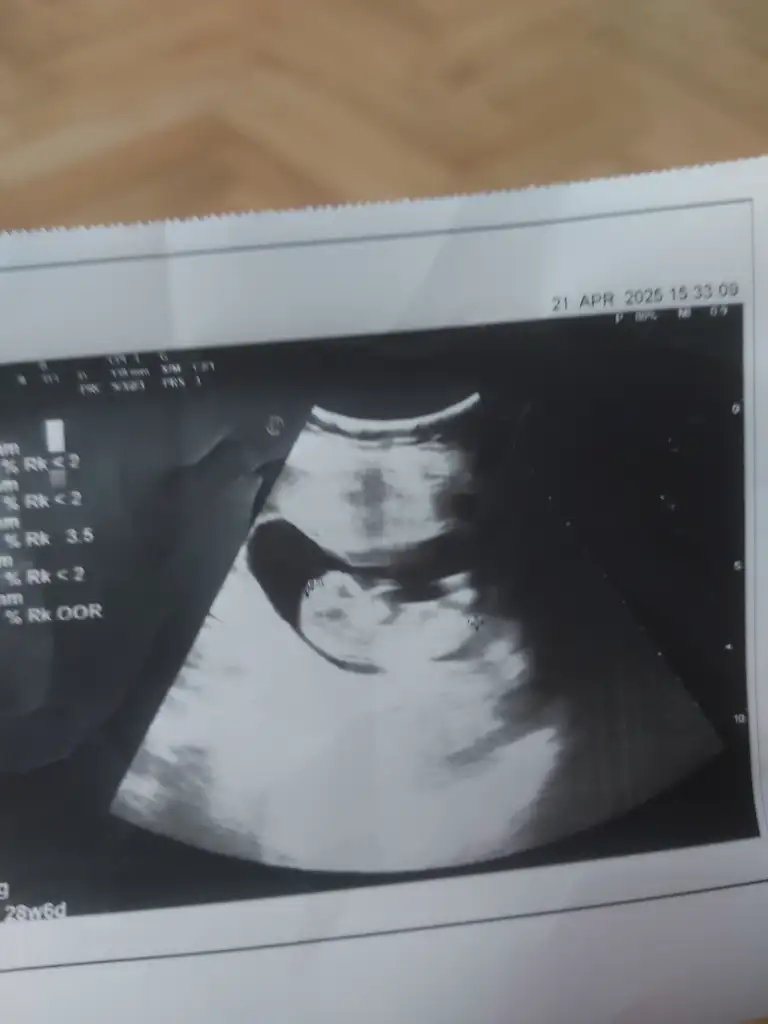

Kıza benziyor kesesi de öylemrb kizlar cok merak ediyorum cinsiyetini ve sizin dusuncenizide merak ediyorum ?

Karindan bakildi 8+6 haftalik.

Çok küçükKızlar benimde karından bakıldı sizce nedir